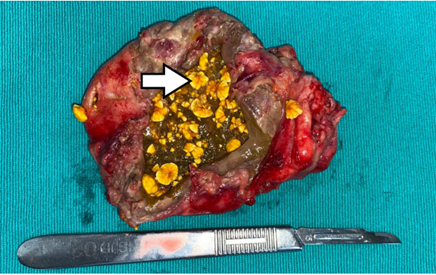

Se presenta el caso de un hombre de 84 años, con antecedentes de hipertensión arterial controlada y enfermedad pulmonar obstructiva crónica, quien consultó por dolor tipo cólico en el hemiabdomen superior, exacerbado por la ingesta de alimentos, irradiado al área periumbilical. Al examen físico había dolor en el hipocondrio derecho, masa palpable y signo de Murphy positivo. Los paraclínicos mostraron leucocitosis leve y transaminasas discretamente elevadas. La ecografía no identificó la vesícula biliar, por lo que se realizó una tomografía computarizada que mostró gas en la pared vesicular y el segmento V del hígado (Figura 1), sugiriendo colecistitis enfisematosa con posible ruptura. Durante la cirugía laparoscópica se identificó un plastrón inflamatorio, por lo que se optó por convertir a cirugía vía abierta; así se encontró una perforación en el tercio inferior de la vesícula y contenido fibrinopurulento (Figura 2). El paciente evolucionó favorablemente, recibiendo alta tras seis días. El análisis histopatológico confirmó inflamación severa, necrosis focal y hemorragia reciente en la pared vesicular (Figura 3).